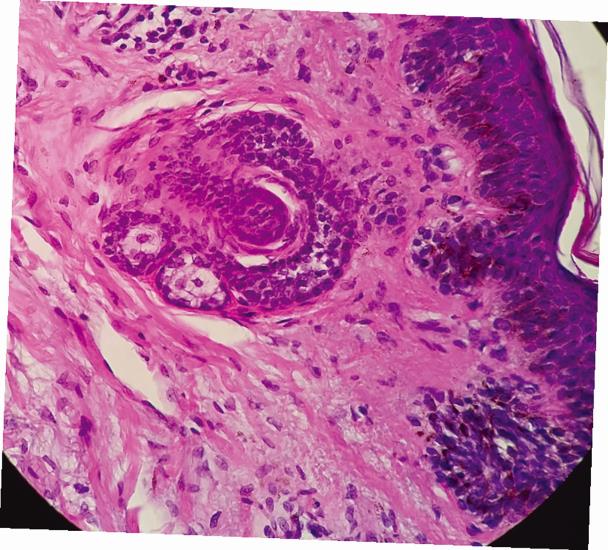

Страшная (может, даже лягушачья?) рожа с выпученными глазами сальных желез, глядящая на нас из волосяного фолликула.